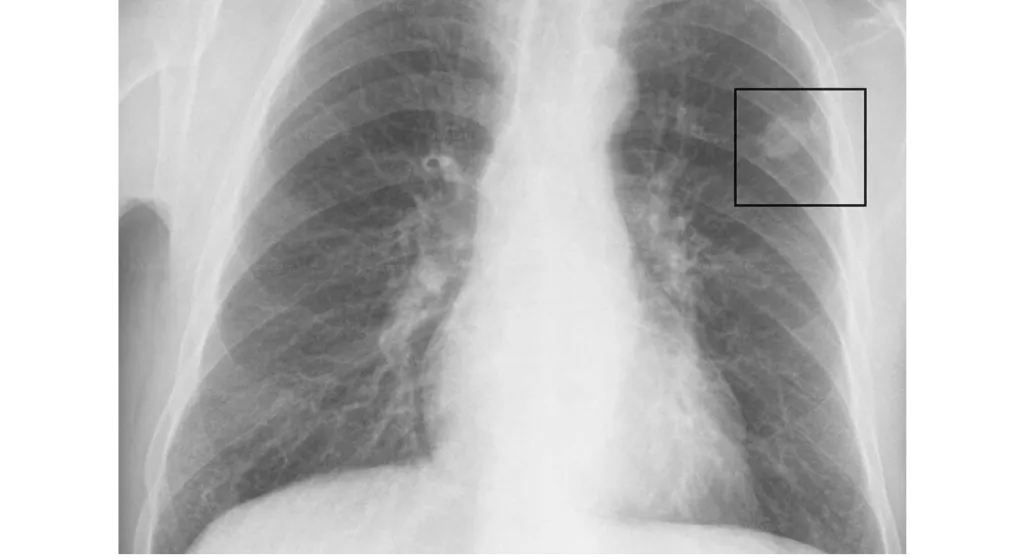

Bệnh phổi trắng, hay còn gọi là hội chứng phổi trắng cấp tính, là một tình trạng viêm phổi nặng và nguy hiểm có thể ảnh hưởng đến mọi lứa tuổi, đặc biệt là trẻ em. Bệnh được đặc trưng bởi những mảng trắng lan rộng trên phổi khi chụp X-quang, do tổn thương phổi do virus, vi khuẩn hoặc các tác nhân khác. Bệnh phổi trắng có thể dẫn đến biến chứng nguy hiểm như suy hô hấp, suy đa cơ quan và thậm chí tử vong, do đó việc tìm hiểu về tiên lượng sống của bệnh nhân là vô cùng quan trọng.

Kết quả X quang phổi trắng